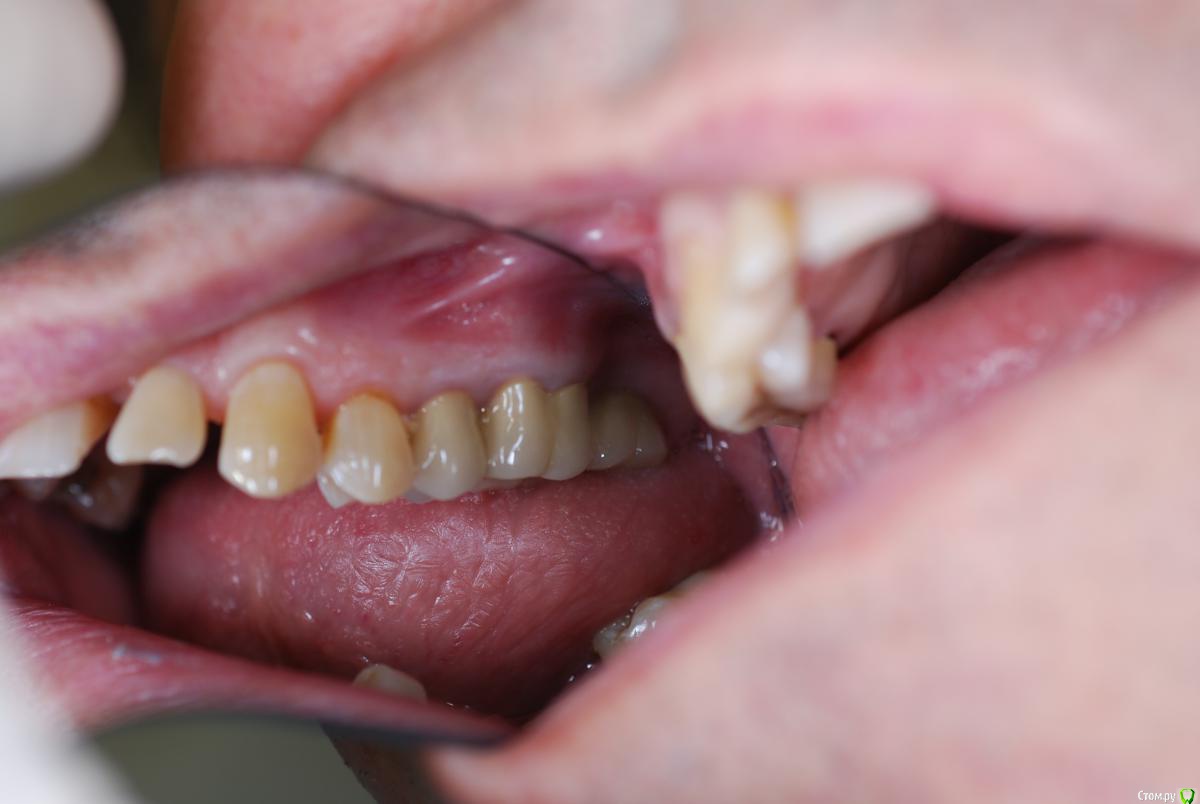

Популярный пост carloss Опубликовано 3 декабря, 2015 Популярный пост Поделиться Опубликовано 3 декабря, 2015 http://savepic.su/6646447.jpg http://savepic.su/6630063.jpg сегодня http://savepic.su/6681262.jpg http://savepic.su/6664878.jpg http://savepic.su/6619823.jpg http://savepic.su/6658734.jpg без чисток и тд.. десять лет вообще не ходила к стоматологу 31 Ссылка на комментарий

carloss Опубликовано 3 декабря, 2015 Автор Поделиться Опубликовано 3 декабря, 2015 (изменено) Можно подробнее, сделали ампутацию? да, раньше часто делал, но обычно срезал один из щечных корней.. большинство стоит до сих пор, правда тут, и шестерка и пятёрка экстремально без феррула, кроме ампутации тока вот, чтобы не обольщались - антагонисты, концевой бюгель)) Изменено 3 декабря, 2015 пользователем carloss Ссылка на комментарий

Doc Опубликовано 6 декабря, 2015 Поделиться Опубликовано 6 декабря, 2015 Через много лет плохой гигиены и жуткого прикуса, 20 июля 2012 года. 9 Ссылка на комментарий